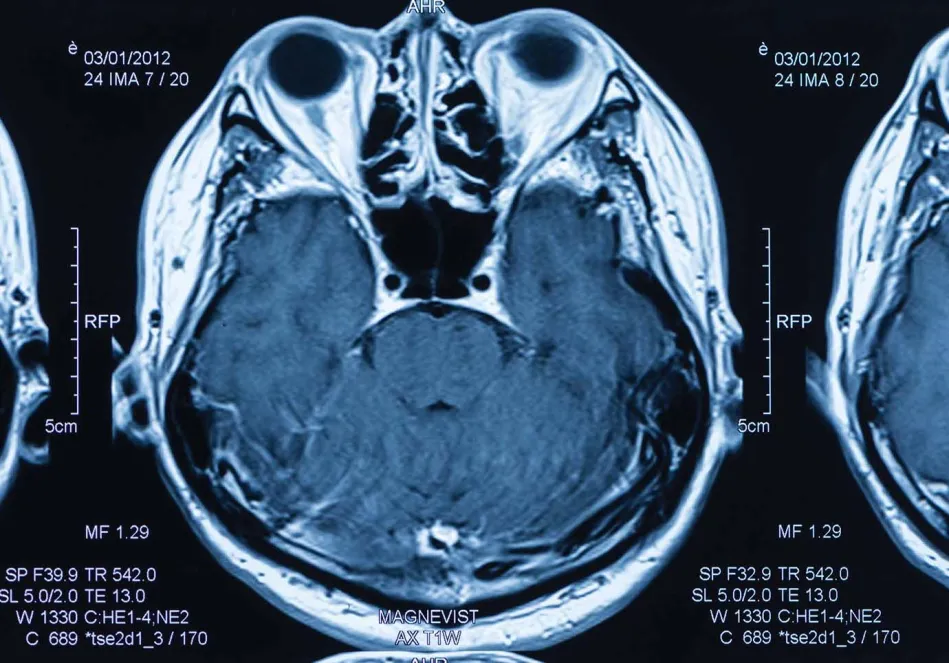

According to the World Health organization, in many medical cases worldwide, clinical considerations are not enough to make a correct diagnosis. radiology, or diagnostic imaging, allows doctors to see inside the body, providing detailed information that is crucial for proper disease diagnosis. As the World Health Organization put it, "diagnostic imaging is a prerequisite for the correct and successful treatment of at least a quarter of all patients worldwide."

The problem? Two-thirds of the world's population lacks access to basic radiology services, whether in the form of X-rays, ultrasounds, CAt scans, magnetic resonance or other procedures -- what HealthManagement.org describes as the "global radiology gap that now poses a threat to public health."

Using artificial intelligence, Rology works to bridge this gap through an on-demand, web-based teleradiology platform that instantly and remotely matches radiology images originating from hospitals with professional radiologists in different parts of the globe. Rology can be easily accessed by radiologists worldwide and doesn't require special hardware.

Rology operations follow three main steps: upload, match and report. the hospital uploads the patient's medical images onto the system. Based on the first auto analysis, Rology then matches the scan with the optimal radiologist, depending on availability and subspecialty. Afterward, the radiologist writes the final diagnostic report and sends it back to the hospital through a quality control process.